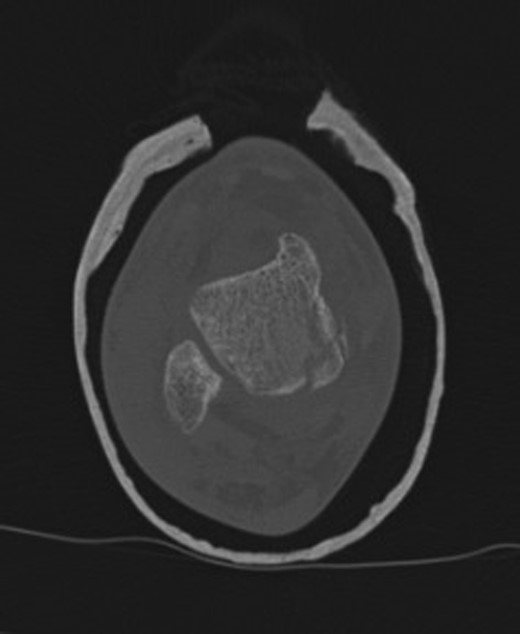

The patient subsequently underwent a manipulation under anaesthesia and POP application of his left distal tibia and right ankle to correct the talar displacement. Despite this, post-operative radiographs of the right ankle showed persistent widened medial tibio-talar joint, and the patient developed considerable right ankle pain and soft tissue swelling which did not correspond with the initial radiograph findings. Magnetic resonance imaging (MRI) of the right ankle joint was performed which revealed extensive marrow oedema through the medial malleolus epiphysis and the medial body of the talus. There was evidence of disruption of the medial cortex of the talus which explained the widened medial tibio-talar joint (Fig. 2). No disruptions of the epiphyseal plates or ligamentous structures were identified. The injury around the tibio-talar joint was identified as an undisplaced fracture through the postero-medial talus with a corresponding ‘kissing’-type lesion of the inner surface of the medial malleolus with gross soft tissue oedema. In view of the overlooked skeletal injury, a further computer tomography (CT) scan of the ankle joint was performed which confirmed a fragmented undisplaced fracture of the postero-medial aspect of the talus, with the anterior subtalar joint remaining intact and an undisplaced fracture through the medial malleolus (Fig. 3).

Right ankle CT axial view demonstrates undisplaced compression fracture of the medial body of the talus.